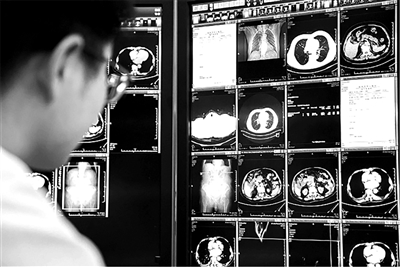

丽水市中心医院放射科腹部组组长周永进检查病人CT片

一天看100多张胸部CT,每一张胸部CT片又相当于把一块面包切成了200片,需要一片一片认真检查。这是过去11年,丽水市中心医院放射科医生周永进每天的工作。

不过最近,他多了一个超级助手:医疗AI。